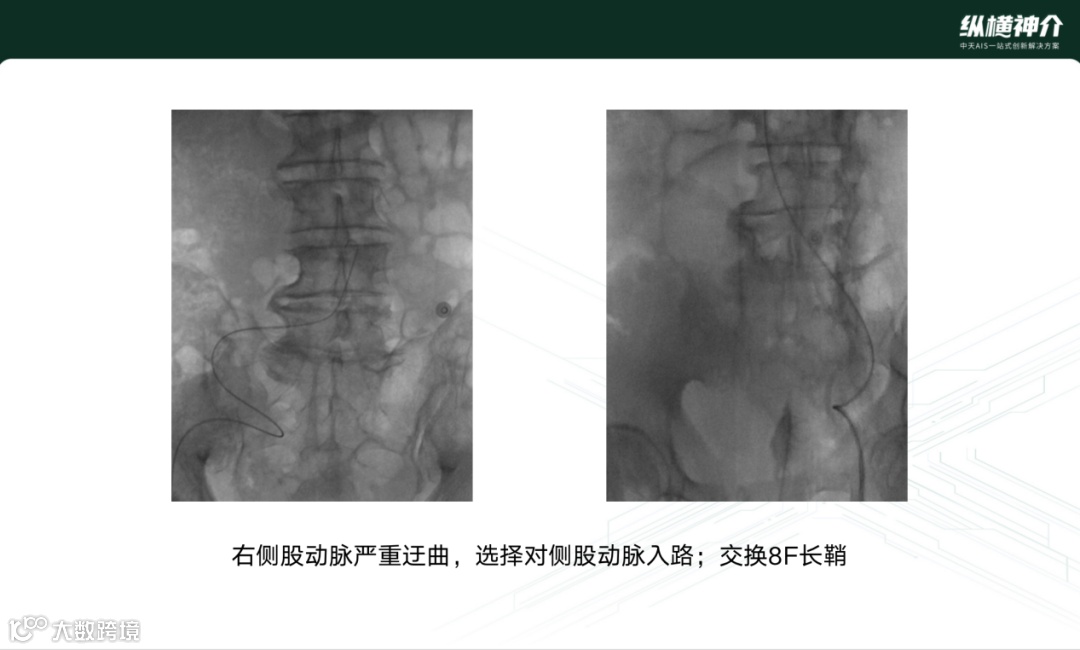

这是一例右侧股动脉严重迂曲,选择对侧股动脉入路,交换8F长鞘,为远端的血管治疗建立了可靠的血管通路。